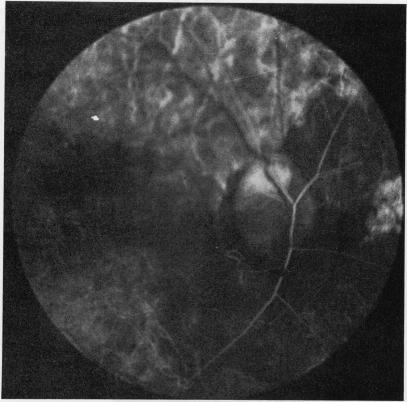

Anterior ischaemic optic neuropathy. I. Terminology and pathogenesis.

Br J Ophthalmol. 1974 Dec;58(12):955-63. doi: 10.1136/bjo.58.12.955.